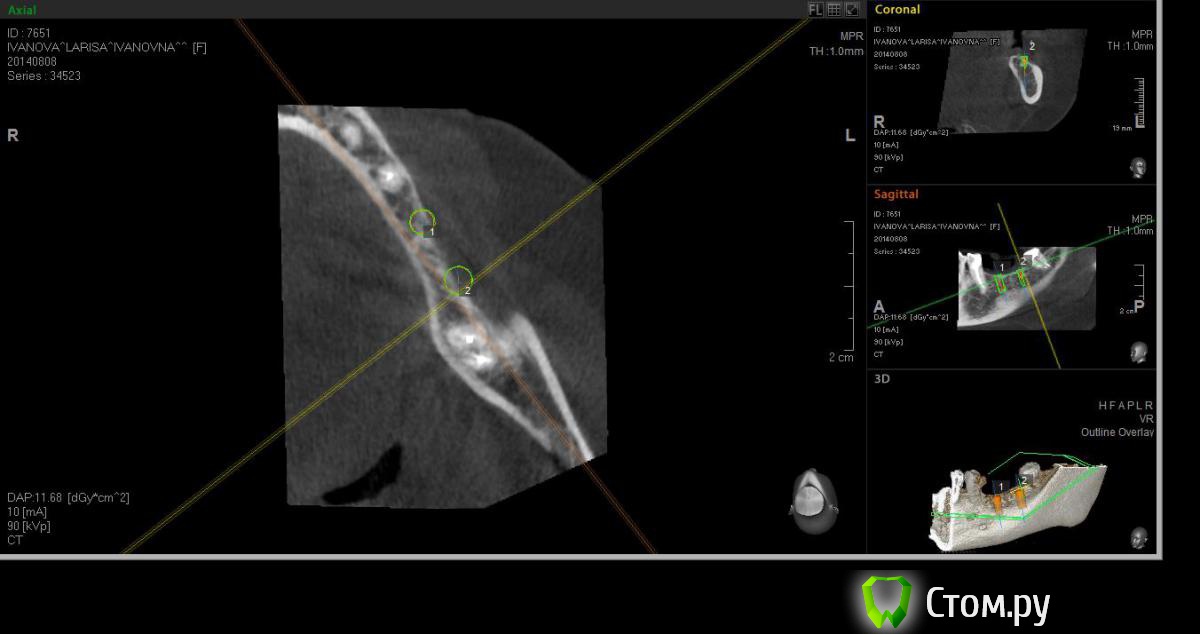

Neilrus Опубликовано 19 августа, 2014 Поделиться Опубликовано 19 августа, 2014 (изменено) Здравствуйте, форумчане-коллеги ) подскажите в очередной раз, пожалуйста.Возник вопрос, для опытных, безусловно, простой, помогите добрым советом.планируем имплантаты в область 36, 37. Длина никак больше 8 не входит, до нерва 10 с копейками и боюсь слишком тонкую кортикалку подязычно оставить.Расщепление из-за формы гребня не думаю, что получится, что-нибудь отломаю точно, хочу поставить как на фотографиях с нкр, голые витки вестибулярно перекрыть еволюшином толстым, припинить весибулярно и язычно если подлезу, либо подошью там.Как вы считаете, рабочая стратегия? Основной вопрос, могу я тут 100% ауто использовать? Объем же не большой, тут со сверления наберу, либо скребочком в зоне операции, заодно и принимающее ложе освежую это же сосидж? ничего не перепутал? И по поводу диаметров, 36 будет 3,75х8, а 37 4,2х8, не кротковаты? Просто у нас только МИС seven пока, либо 8, либо 10 длина. В 37 можно и 5 диаметр поставить, но опять же тонкая язычно остается. По той же причине отказался от длины 10 в 36зубе. Изменено 19 августа, 2014 пользователем Neilrus Ссылка на комментарий

Neilrus Опубликовано 26 августа, 2014 Автор Поделиться Опубликовано 26 августа, 2014 (изменено) +2 )) Во-первых, фиксация у Севена лучше, конечной фрезой на 50 оборотах понемногу наберете ауто. Если есть АСМ или Джилли - еще получите в области ретромолярки. Во-вторых, кости (на самом деле) "немного" больше, чем показывает конусник (это тоже плюс). Поэтому можно и 8, и 10 со стопером или под контролем. Ставьте на 0,5-1 ниже язычной. Выше ставить и обсыпать не рекомендую - разве что только под жесткую мембрану, иначе все уйдет. Язычно я бы не смещался, ставил как запланировано, по шаблону. И в обл. 37 до нерва более 11, так что все будет ОК. Потом придется поработать с мягкими тканями. Удачи!Спасибо. Поставил в итоге два севена десятки, у м4 резьба у шейки никакая по мне так, а шейка тут важна. Наклонил все равно слегка язычно, никуда не провалился, парестезии нет, немного у медиального было ей больно при дотягивании на 25 нютонах, сделал полоборота назад, ауто, потом микс с мр3, эволюшн три пина язычно, два вестибулярно. Швы в пн снимаю, пока полет нормальный, отек уже почти сошел. И по поводу взятия ауто, насколько я правильно понял всех лекторов моих, забор во время бурения только промежуточными сверлами, пилотное и финишное сверление всегда с водой. Нет? Изменено 26 августа, 2014 пользователем Neilrus Ссылка на комментарий